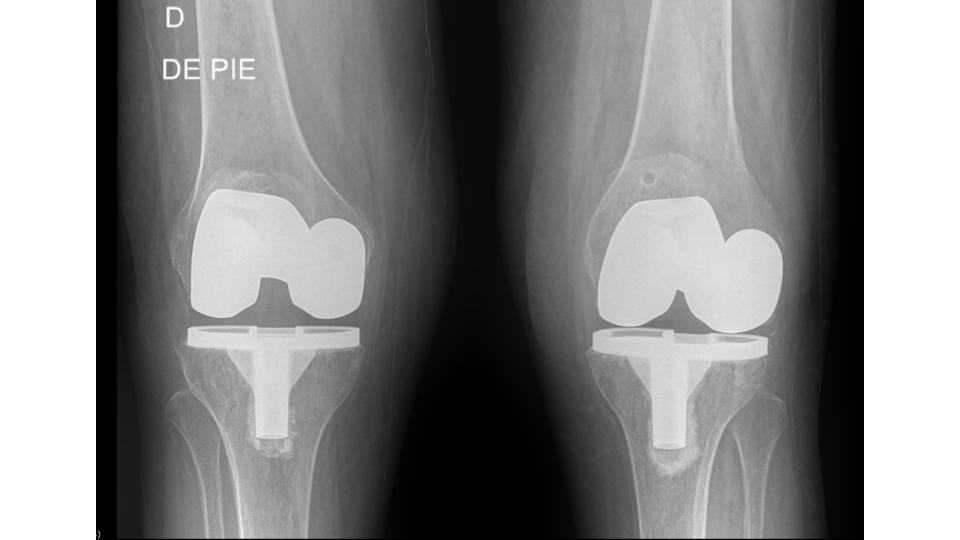

Se analizó un total de 36 prótesis en 32 pacientes. De este total, 25 (78 %) fueron de sexo femenino y 7 (22 %), de sexo masculino. Cuatro pacientes presentaron reemplazo bilateral (Figs. 1, 2 y 3).

Figura 2. Radiografía anteroposterior postoperatoria tras artroplastia total de rodilla con alineación mecánica y prótesis cementada modelo SigmaTM (DePuy, Synthes/Johnson & Johnson, Warsaw, IN, EE. UU.).